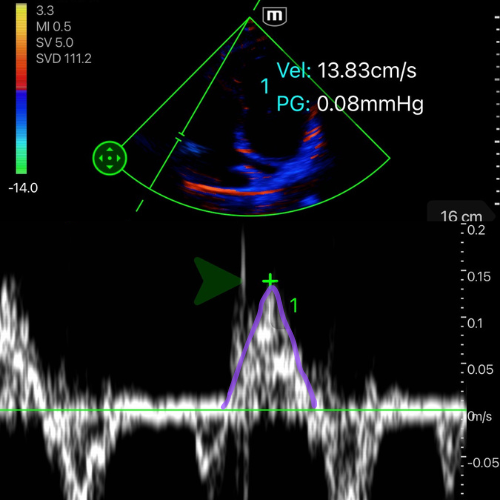

Onde S’ tricuspide (vitesse Doppler tissulaire) : normale > 10 cm/s.

🖥 Vue : se placer en A4C centrée VD.

🎯 Cible : repérer l’anneau tricuspide latéral (jonction VD–OD, paroi libre).

🎛 Mode Doppler tissulaire : activer le TDI (Tissue Doppler Imaging), placer le curseur sur l’anneau tricuspide latéral, puis activer le mode Doppler pulsé (PW).

📈 Acquisition : enregistrer le spectre Doppler tissulaire ; on doit visualiser :

une onde S’ en systole (le pic de l'onde positive – au dessus de la ligne de base)

suivie des ondes E’ et A’ en diastole (ondes négatives – en dessous de la ligne de base).

-

📏 Mesure : mesurer la vitesse maximale de l’onde S’ (en cm/s).

✅ Valeurs de référence :

S’ ≥ 10 cm/s → fonction systolique du VD préservée

S’ < 10 cm/s → dysfonction systolique du VD

![]()